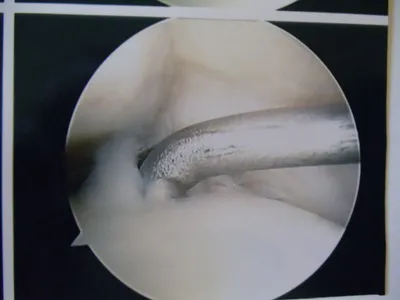

Intraop arthroscopy pic of OCD afer debridement and during microfracture.

Intraop pictures of OCD of the talus after debridement and during microfracture.